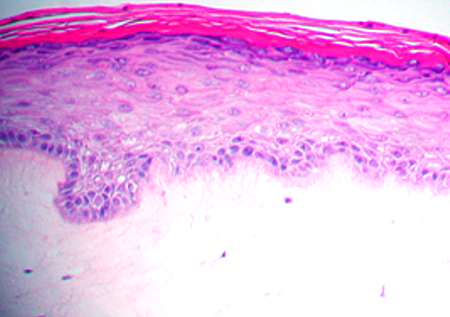

Psoriasis is a chronic inflammatory skin disease characterized by epidermal hyperplasia (Acanthosis) with elongated ridges and abnormal differentiation of epidermal keratinocytes, dermal angiogenesis, abnormal accumulation of polymorphonuclear leukocytes, infiltration of activated T cells and dendritic cells, and increased cytokine levels. MatTek has developed in vitro model of Psoriasis to enable the study of the disease, and to screen therapeutic candidates for safety and efficacy.

Histology: 8-12 cell layers plus stratum corneum (basal, spinous, and granular layers).

The tissue model closely parallels lesional psoriatic human tissues in terms of morphology and cytokine expression. This model provides researchers with a useful, in vitro means to study psoriasis biology phenomena.

MatTek’s psoriasis model mimics the morphology and progression of psoriasis in vivo, making it a valuable tool for the study of the disease, and evaluation of the efficacy of therapeutic candidates. |